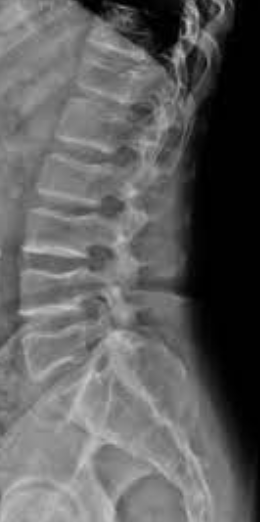

위의 이미지는 전만증 환자의 엑스레이입니다. 물론 X-ray 상으로는 허리 곡선이 확연히 휘어져 있는 것을 확인할 수 있습니다. 골반 얘기도 하자면 이 경우 골반의 전방경사가 심해집니다. 또한 이 경우 척추 기립근의 긴장이 심해집니다. 그러나 전만증도 과거에 논의된 적이 있지만 모든 경우가 병리적인 것은 아닙니다. 운동선수들이 자주 보이는 자세이기도 합니다. 일반적인 전만증의 진단 기준은 병리학적 상태의 기준과 다르기 때문에 모든 상황에서 교정이 필요한 것은 아니라고 말씀드릴 수 있습니다. 정기적으로 운동하는 사람들은 필연적으로 생리학적 전만증을 갖게 됩니다. 이 경우 골반의 전방경사를 교정하고 교정을 위해 척추를 곧게 펴주는 것은 추천하지 않습니다. 재발하기 쉽기 때문입니다.후만증